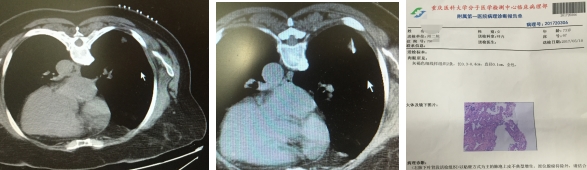

患者xxx,女,71岁,重庆潼南人,院外体检发现右下肺5*5mm大小的孤立结节影。辗转多家医院来我院呼吸科就诊,以求明确诊断。呼吸科李长毅副主任为首的治疗小组,于2017年5月9日,在CT引导下成功精准穿刺活检,最后病理考虑原位腺癌可能,已经转胸外科手术治疗。患者非常幸运,在原位癌极早期明确诊断,并手术切除,可以达到治愈的效果。

呼吸内科作为国家临床重点专科,在近两年积极面对肺部微小结节多发的严峻形式。创新开展肺部微小结节的精准穿刺活检术,取得长足进步。1cm以下肺部微小结节已经作为常规穿刺(国内有报道的穿刺微小结节最小3.2mm,我科最小结节4mm),成功诊断多起早癌、甚至原位癌。在业界获得强烈的反响,充分体现了国家临床重点专科水平。